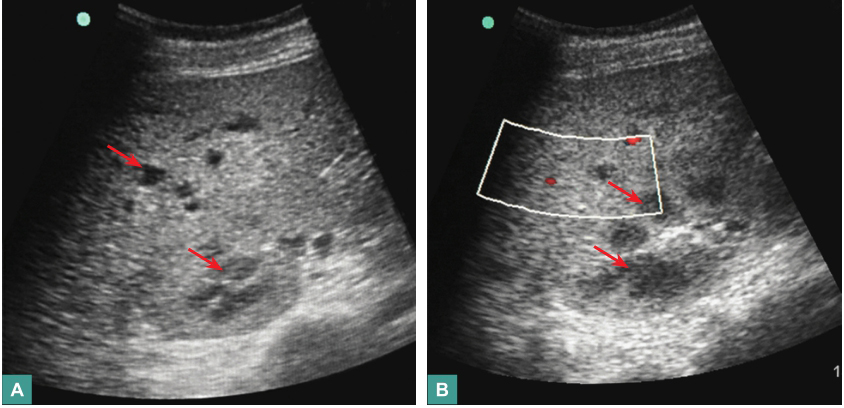

患者入院后,予亚胺培南/西司他丁(1g,每8小时1次)抗感染治疗,辅以磷酸肌酸钠改善心肌代谢,并继续给予抑制胃酸、保护胃肠黏膜、营养支持(滋养型肠内营养联合静脉营养)、调节肠道微生态、保肝等治疗。床旁腹部超声检查发现中等量腹水,置管引流出淡黄色微浑液体1800ml。腹水常规:白细胞计数2548×109/L,多核细胞76%。入院第4日,鉴于患者腹痛无缓解,且有发热(体温达38.5℃),复查CRP 75.1mg/L,外周血WBC 13.1×109/L,N% 83.0%,不排除合并肠道革兰阳性球菌感染可能,遂加用利奈唑胺(600mg,每12小时1次)加强抗感染治疗。治疗1周后复查,血常规:WBC 9.8×109/L,N% 78.0%,Hb 85g/L,PLT 178×109/L;PCT降至0.82ng/ml;CRP 29.0mg/L;腹水逐渐减少,腹水白细胞计数降至803×106/L;肝、肾功能正常。但患者仍有发热(37.5~38.5℃),无畏寒、寒战,上腹痛无缓解且进行性加重。复查肝脏超声见多发低回声病灶较前增大(图4)。考虑患者WBC、CRP、PCT等全身炎症反应指标改善与感染性腹水引流后全身炎症反应有所下降有关,但腹痛、发热无改善,需考虑肝脏病灶可能为细菌、真菌混合感染,遂加用米卡芬净(150mg,每天1次)经验性抗真菌治疗,并继续超声动态监测肝脏病灶变化(如有液化,可考虑穿刺引流培养以明确病原学诊断)。虽然血液及腹水肿瘤标志物检测没有阳性发现,但仍不能排除肿瘤引起的腹痛及发热,可待肾功能恢复后,择期行腹部增强CT协助诊断,必要时可待凝血功能进一步好转后行肝结节活检以明确诊断。

入院后,患者中上腹闷痛、腹胀无缓解,交替排黑便(50~550ml/d)和黄软便,血红蛋白最低降至65g/L。入院第11天,患者出现腹痛加剧,呕血400ml,排柏油样便量约600ml,意识淡漠,血压降至70/40mmHg,血红蛋白30g/L,予输血、升压处理后急行床旁胃镜检查,见胃黏膜大片状剥脱,黏膜下血肿形成,部分可见血管裸露,肌层显露,胃腔内大量血块形成,内镜下无法止血。立即全麻下急行剖腹探查术,术中见胃大部分区域缺血坏死,胃腔扩大明显,内可见大量血凝块,胃黏膜大片剥脱,累及浆膜层,肝表面见多发黄色脐乳样结节,遂行全胃切除+食管空肠Roux-y吻合+肝脏结节活检术。术后,患者循环系统逐渐稳定,血红蛋白升至100g/L。但术后第3天,患者再发中腹部闷痛,体温37.8℃,外周血WBC 17.8×109/L,CRP 123.00mg/L,腹腔引流液培养出热带念珠菌和屎肠球菌,遂继续予亚胺培南西司他丁钠、利奈唑胺联合米卡芬净抗感染治疗。复查腹部CT,示肝内低密度灶较前增多、增大(图5),肠系膜血管CTA未见异常。

图5腹部CT表现

腹部CT见肝内多发低密度灶较前增多,增强扫描病灶无强化

引自:内科疑难病例解析.第1版.ISBN:978-7-117-26559-1.主编:朱鹏立 陈愉生